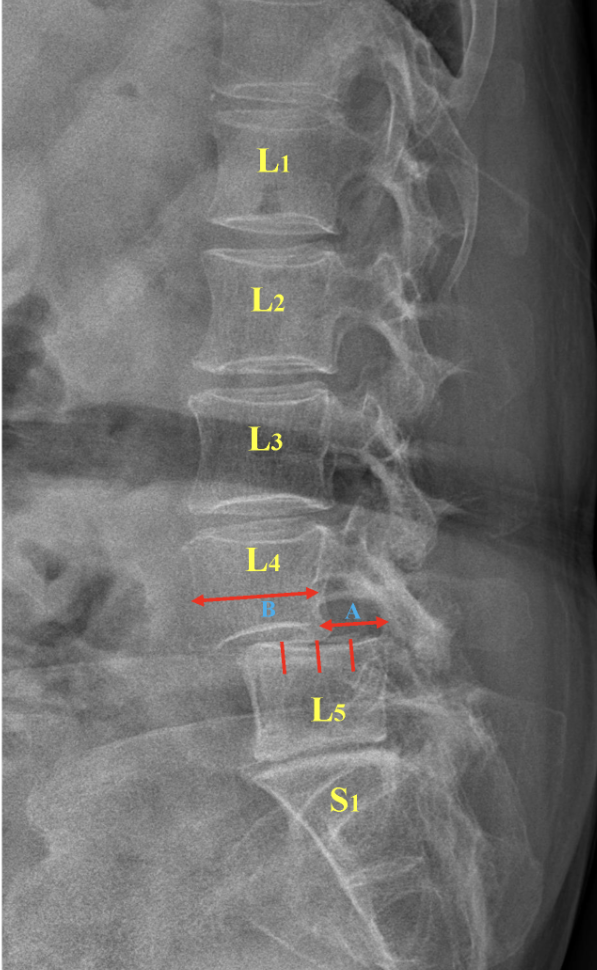

What exactly does slipping mean?

Slipping simply refers to a vertebra moving out of alignment with the vertebra above and/or below it. It does NOT mean slipping out into an abyss or some sort of black hole - It’s much less scary than it actually sounds.